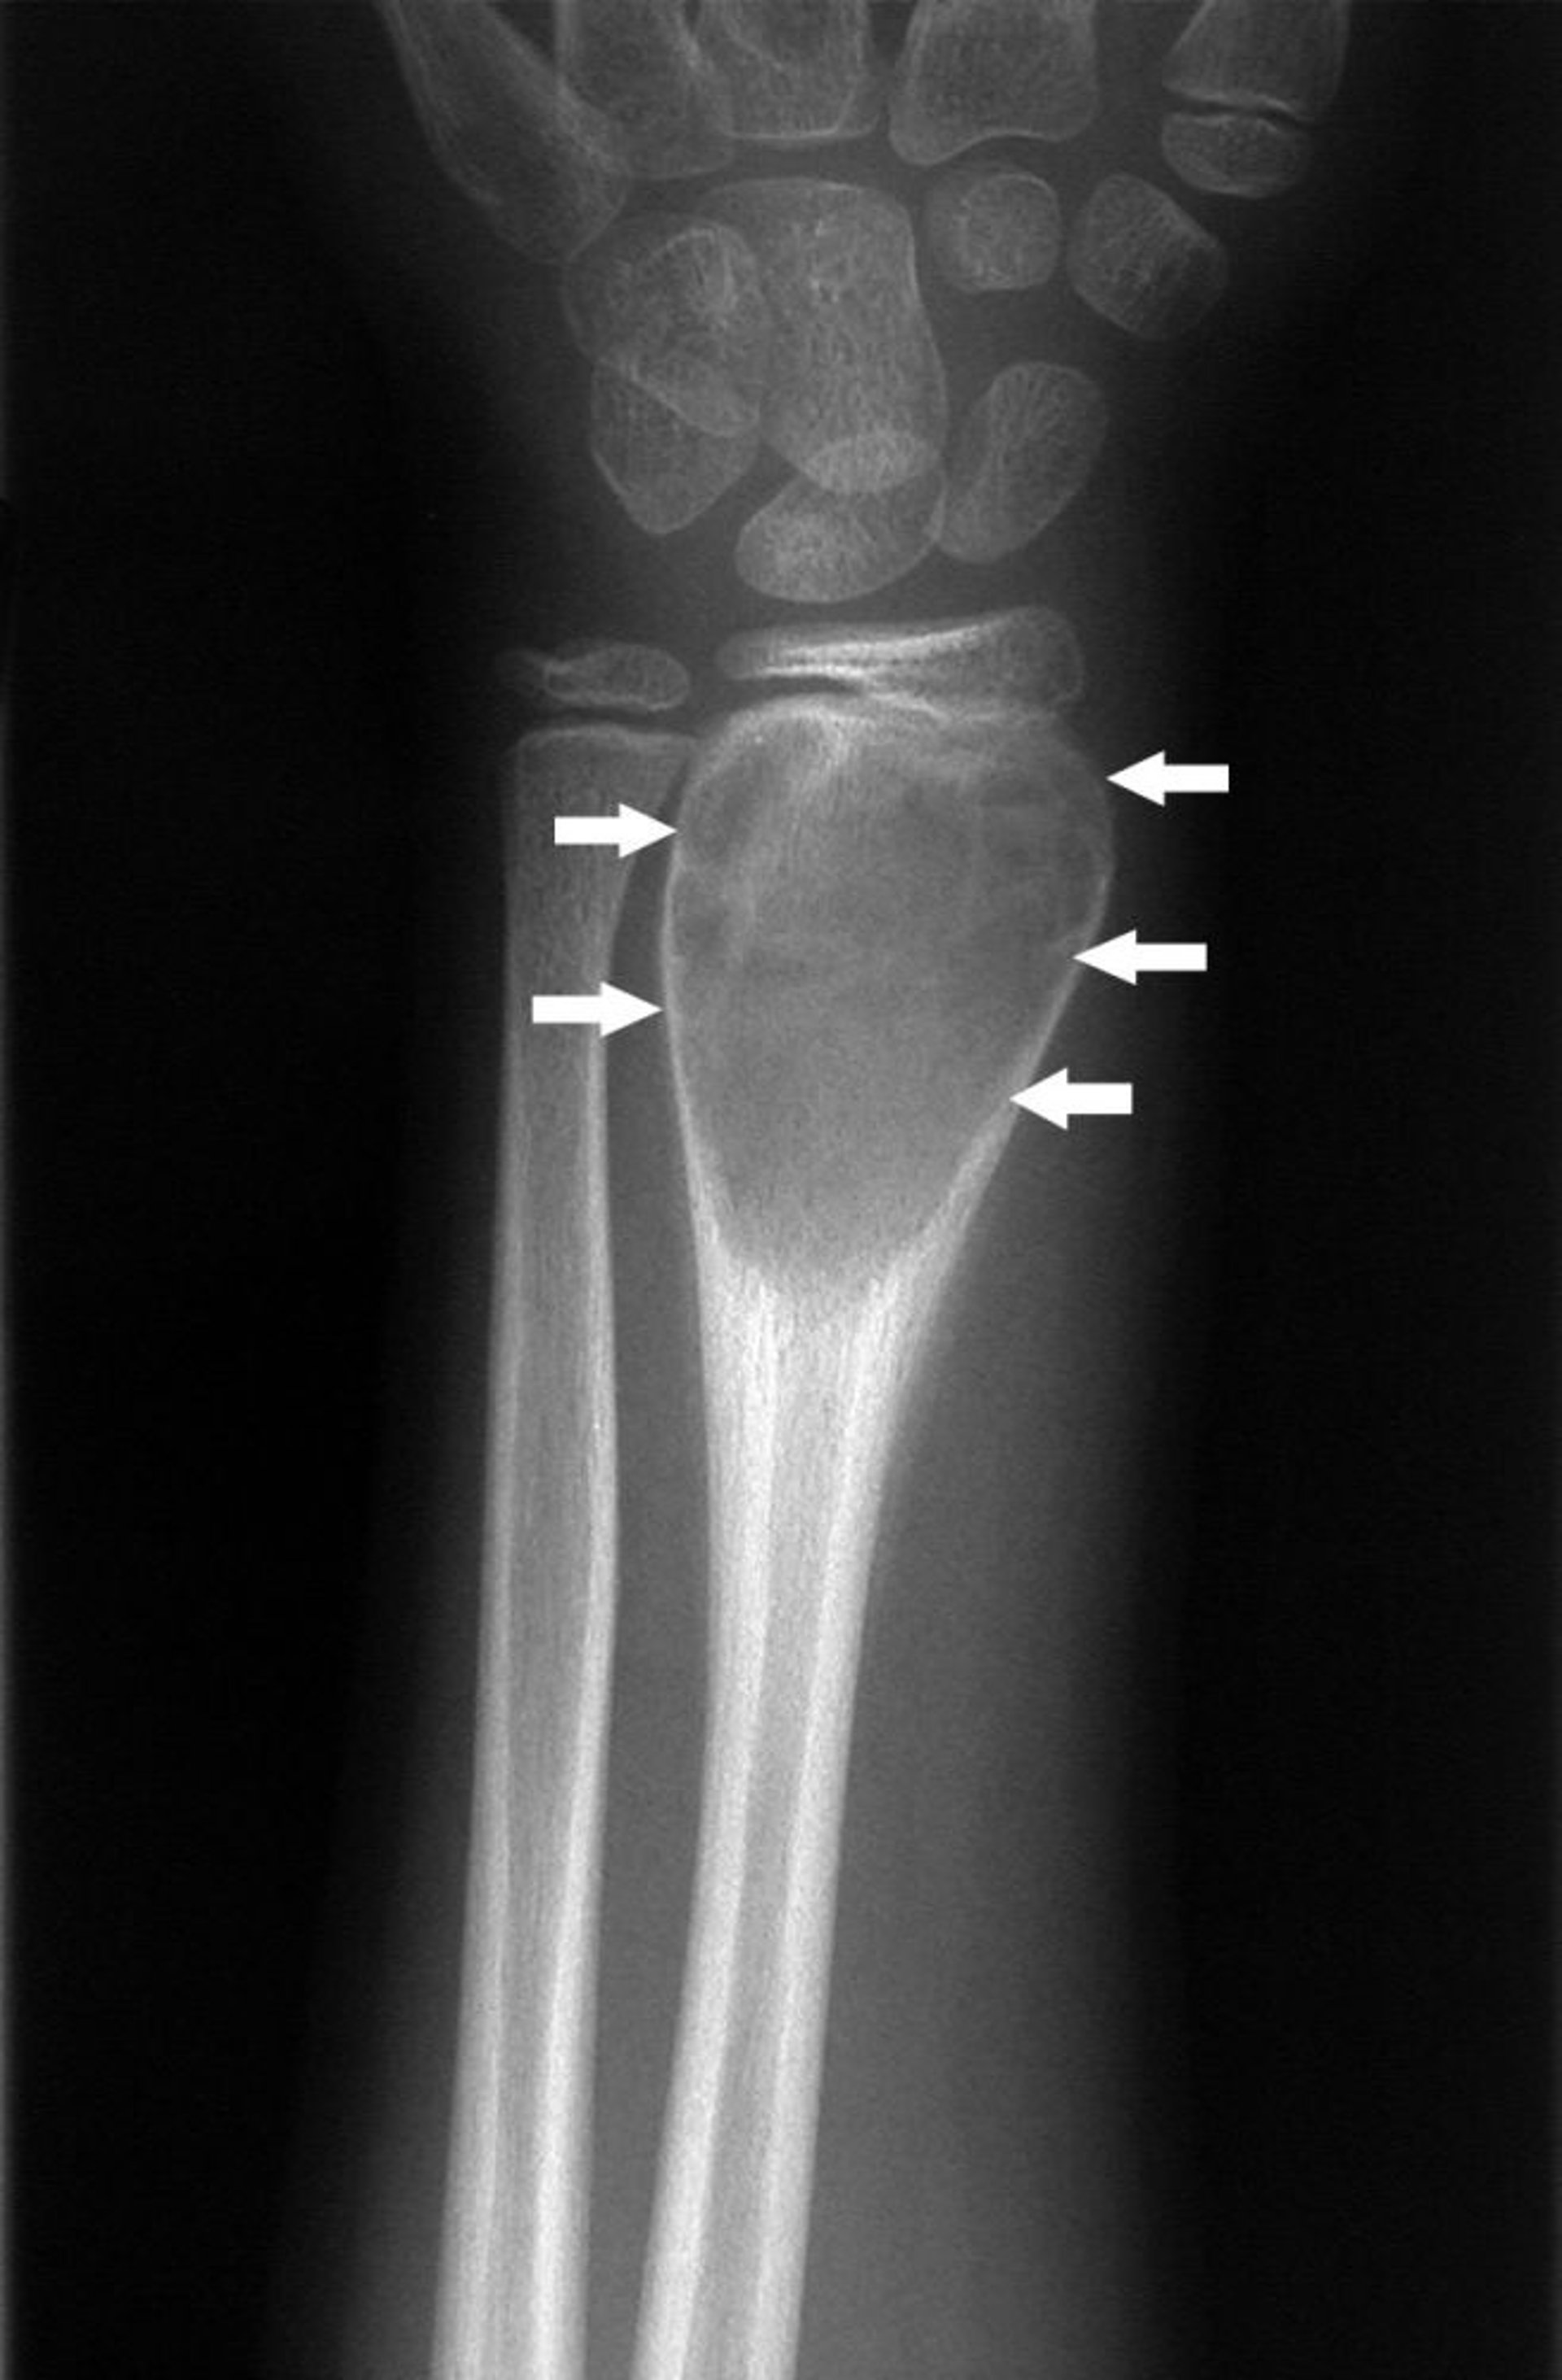

Aneurysmatische Knochenzyste am Handgelenk

Auf dieser Röntgenaufnahme eines Handgelenks ist eine aneurysmatische Knochenzyste (Pfeile) zu sehen.

Bild mit freundlicher Genehmigung von Dr. med. Michael J. Joyce und Dr. med. Hakan Ilaslan.